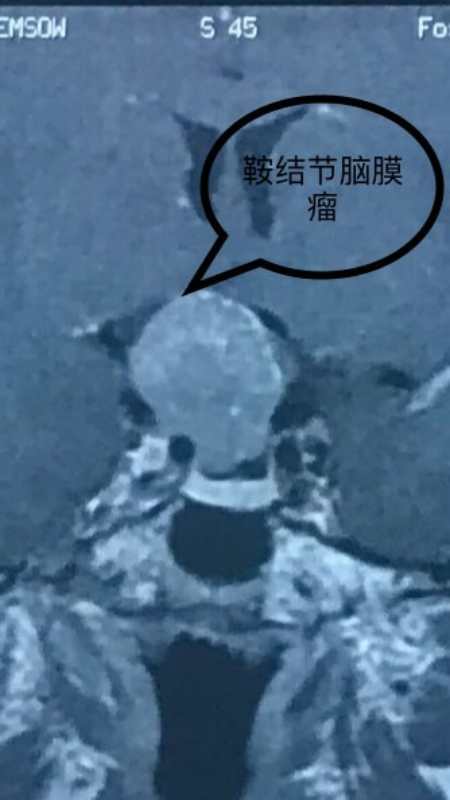

半年前,龚女士开始出现头痛,以为小毛病,平时间断吃一些止痛药,继而出现了双侧视力变得模糊,且头痛越来厉害,严重影响了日常生活,来我院就诊查头颅磁共振确诊鞍区脑膜瘤。肿瘤的基底来源于鞍结节和鞍膈,视神经视交叉及邻近结构严重受压移位,视野图检查右侧眼睛视力全盲,左侧眼睛部分盲(颞侧盲)。